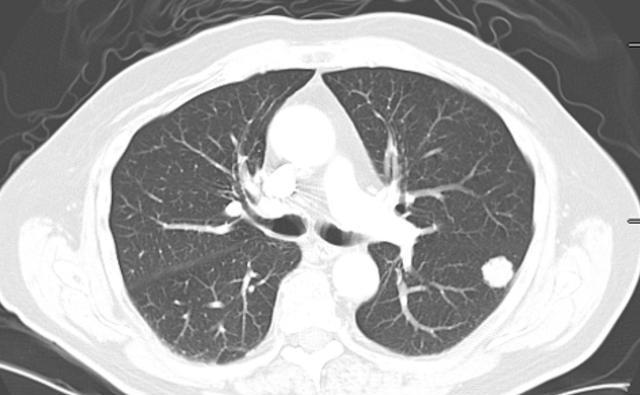

但是一旦肺脏出现问题 , 那么其他器官也会受到影响 , 尤其是越来越多的人患上肺结节 , 身体也会有异常症状出现 , 而且肺结节若是放任不管 , 没有得到好的治疗 , 很容易病情恶化引发肿瘤 。

随后小李去医院进行检查 , 医生给他开了各种各样的单子 , 经过一系列的检查后才得知小李患上了肺结节 , 在医生的询问一下找到病因 , 原来小李这两年里几乎天天抽烟喝酒 。